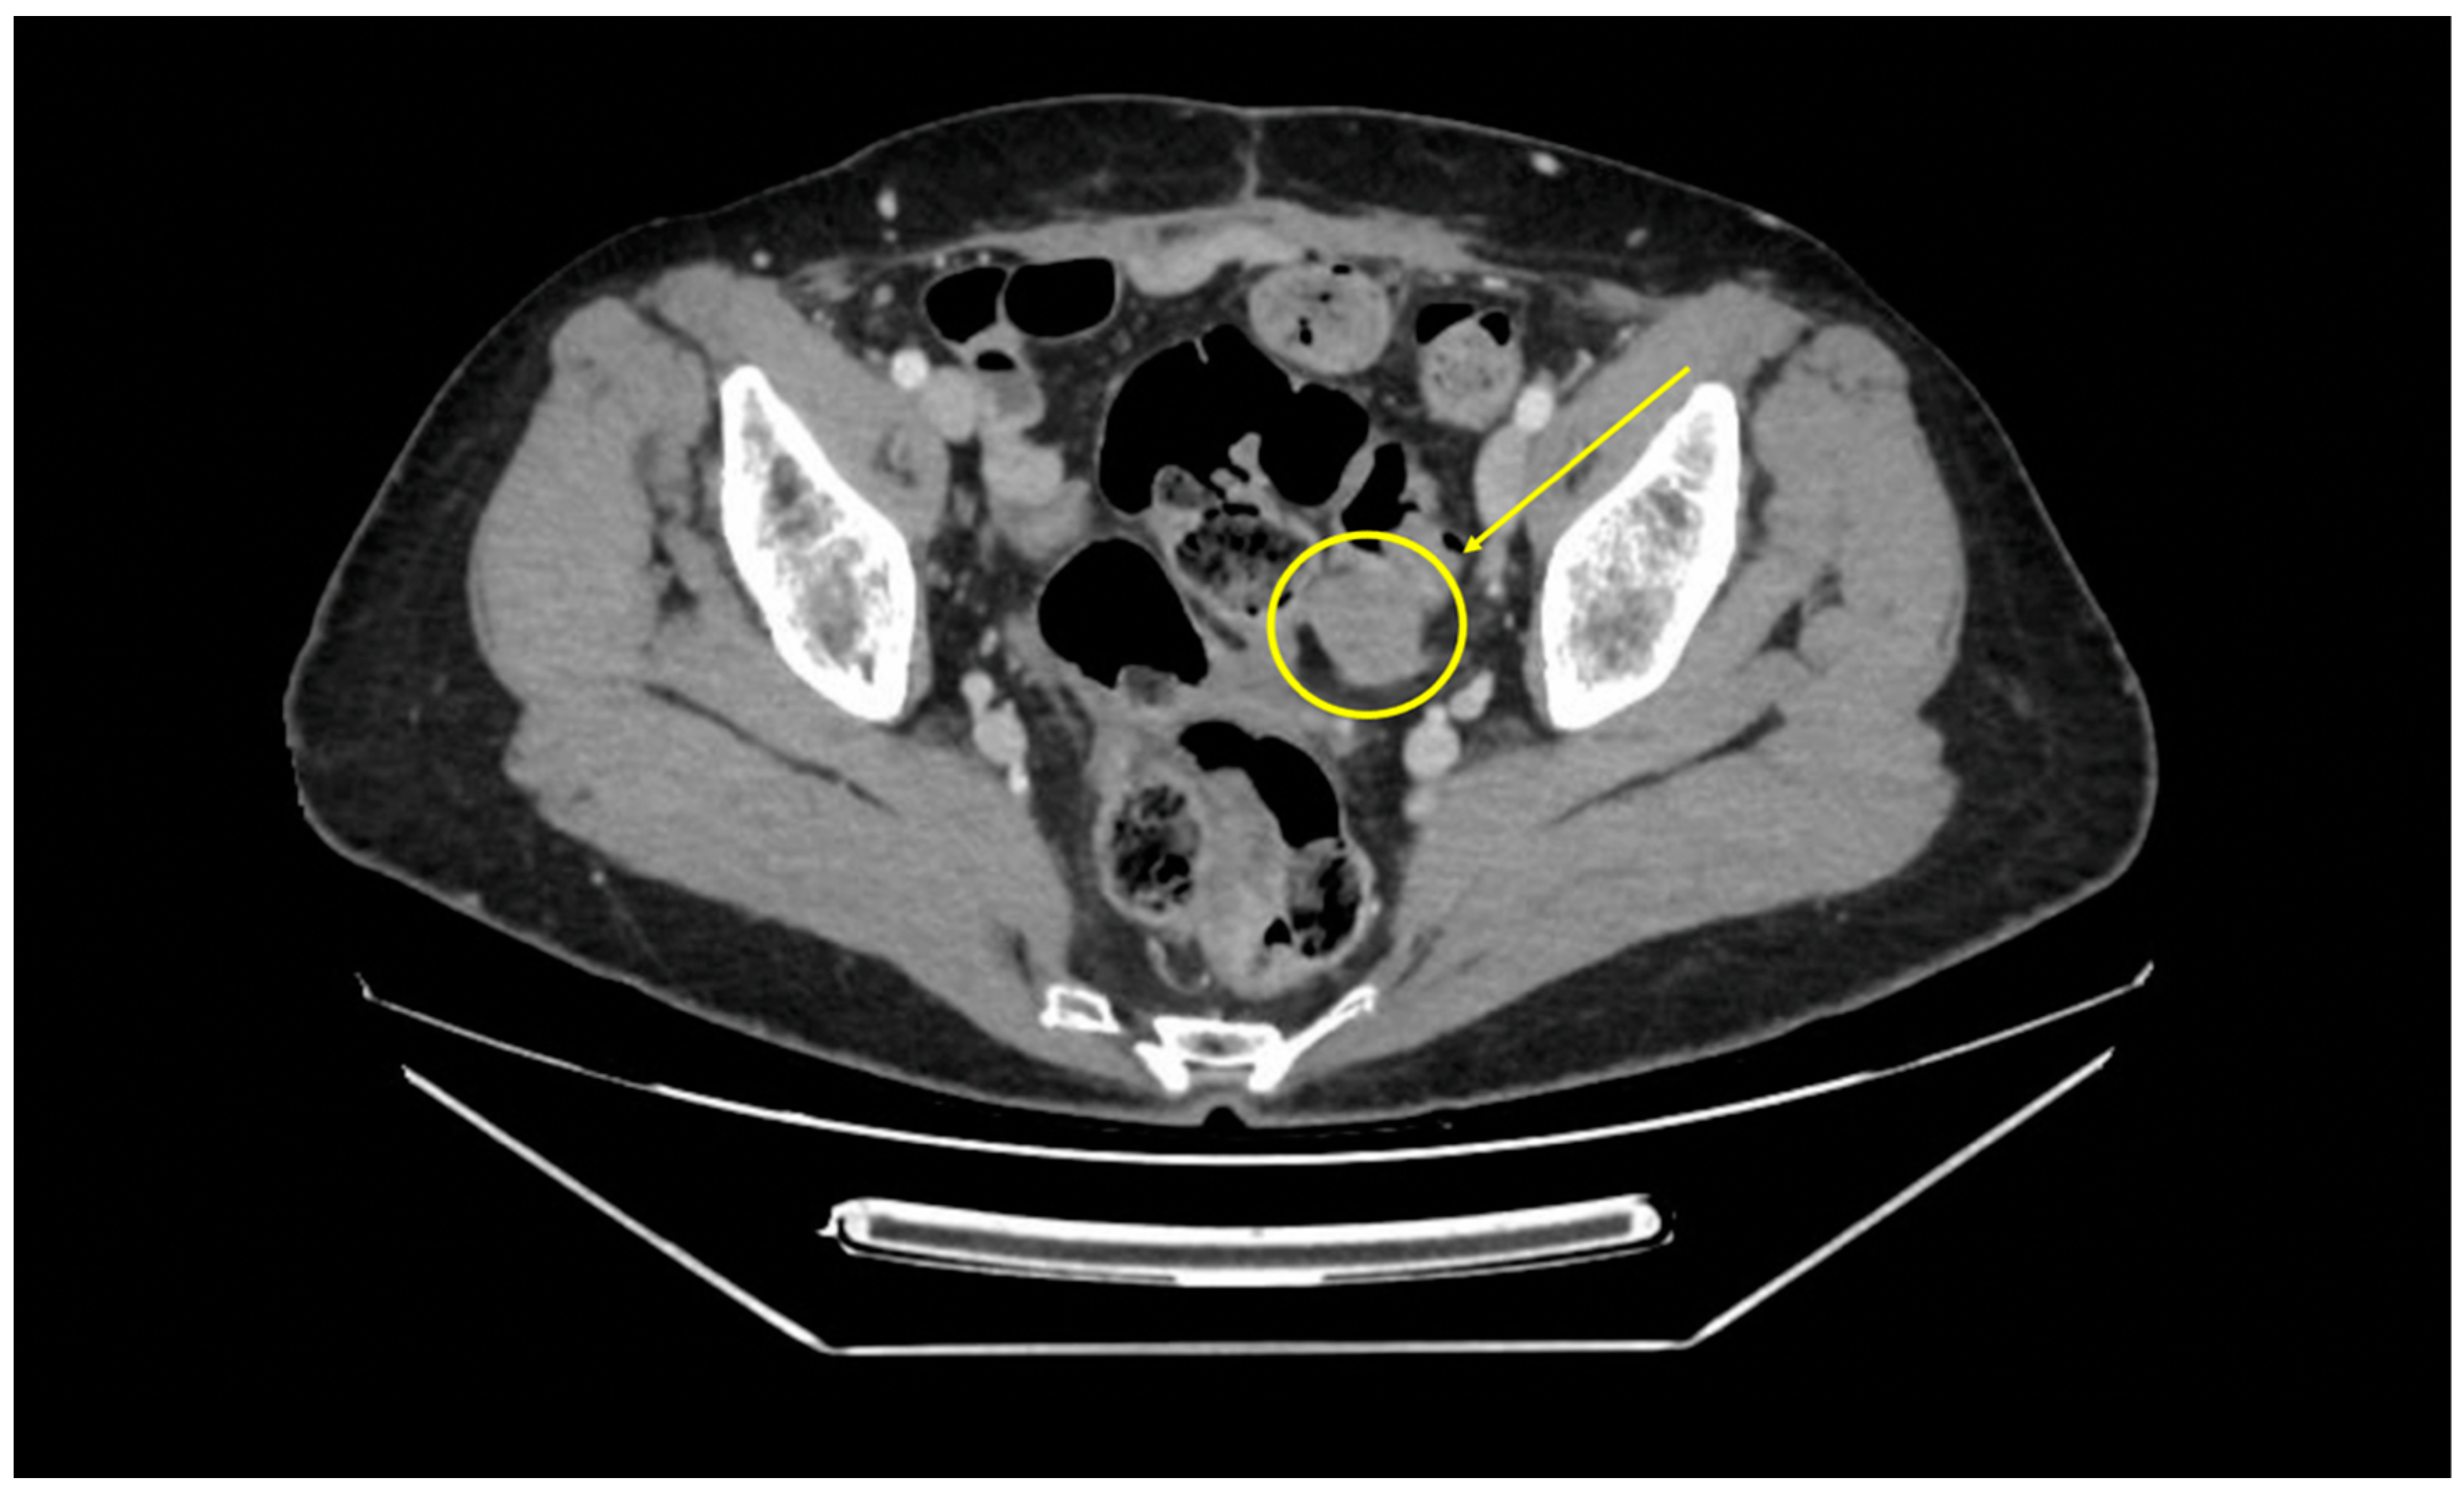

Operative Technique